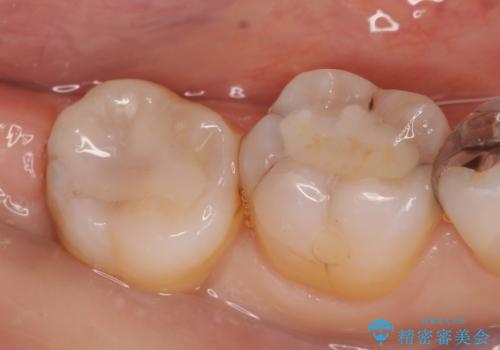

中途半端な継ぎ接ぎの歯を、クラウンでしっかりと処置する

- 古い材料・虫歯を徹底的に除去

→土台を立て直し、クラウンを製作する

神経の無い歯の処置は

①根管治療から

②土台から

③被せものから

やり直す という選択肢がありますが、今回は②を選択しました。費用・期間を優先するか、永続的な安心性を優先するか、その都度相談しましょう。